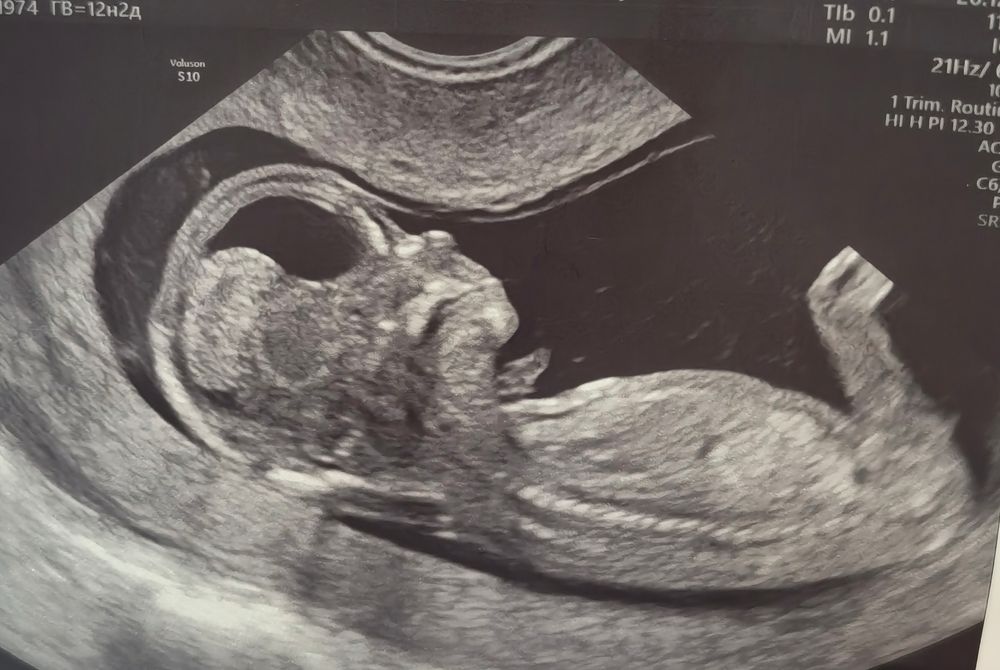

Всё о нашей беременности26 декабря в 12+3 прошла первый скрининг.

Делала в 29ГКБ, и дочь моя не хотела, чтобы её измеряли и оценивали, и пряталась от датчика вовсю. В итоге меня уже изнасиловали этим датчиком, но ребёнка таки измерили и посчитали)

Все риски низкие, и х/а и преэклампсии, ура) но я все равно решила сдать НИПТ.